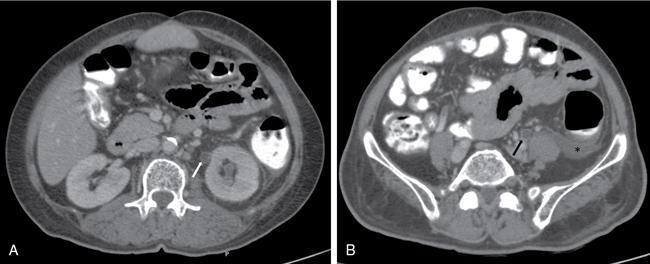

The ureteric wall maybe thickened with focal nodular areas appearing as filling defects on CT. Figs. 10.14.1 and 10.14.2 depict imaging appearance of ureteritis in 2 different patients.

Image

Fig. 10.14.1 A case of left-sided ureteritis. CECT axial images at the level of proximal (A) and distal ureter (B) showing ureteric wall thickening on the left side (white arrow in A and black arrow in B). The patient also had left-sided pyelonephritis with thickening of left pararenal fascia and fluid along left paracolic gutter (asterisk).